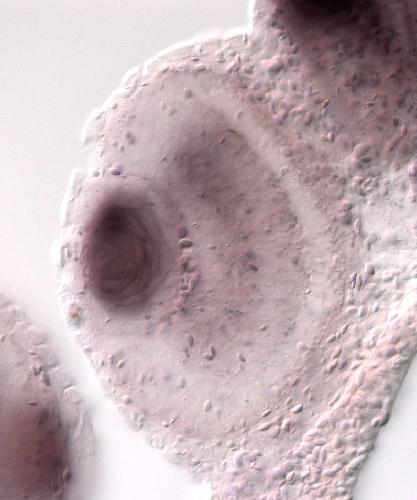

il6st

interleukin 6 cytokine family signal transducer

il6st is a membrane‑bound signal‑transducing receptor subunit that partners with cytokine‑specific α‑chains to form functional receptors for interleukin‑6 family ligands, activates JAK/STAT pathways, a...[+]